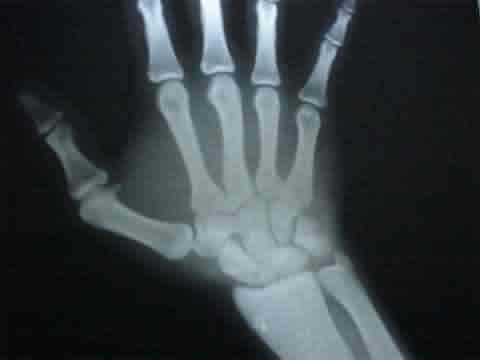

A consecuencia de cogida y revolcón en tentadero reciente, examinamos al novillero gaditano que presentaba grandes molestias en su mano derecha.

Tras estudio y Rx. se le diagnostica una grave fractura de escafoides que asienta sobre una mano muy sufrida por causa de la espada y que ya de antemano presentaba una artrosis post traumática que va a más.

Hace pocos meses ya exploramos esta mano ( ver cogidas 2002 ) que ya presentaba síntomas artrósicos a simple vista y radiológicos